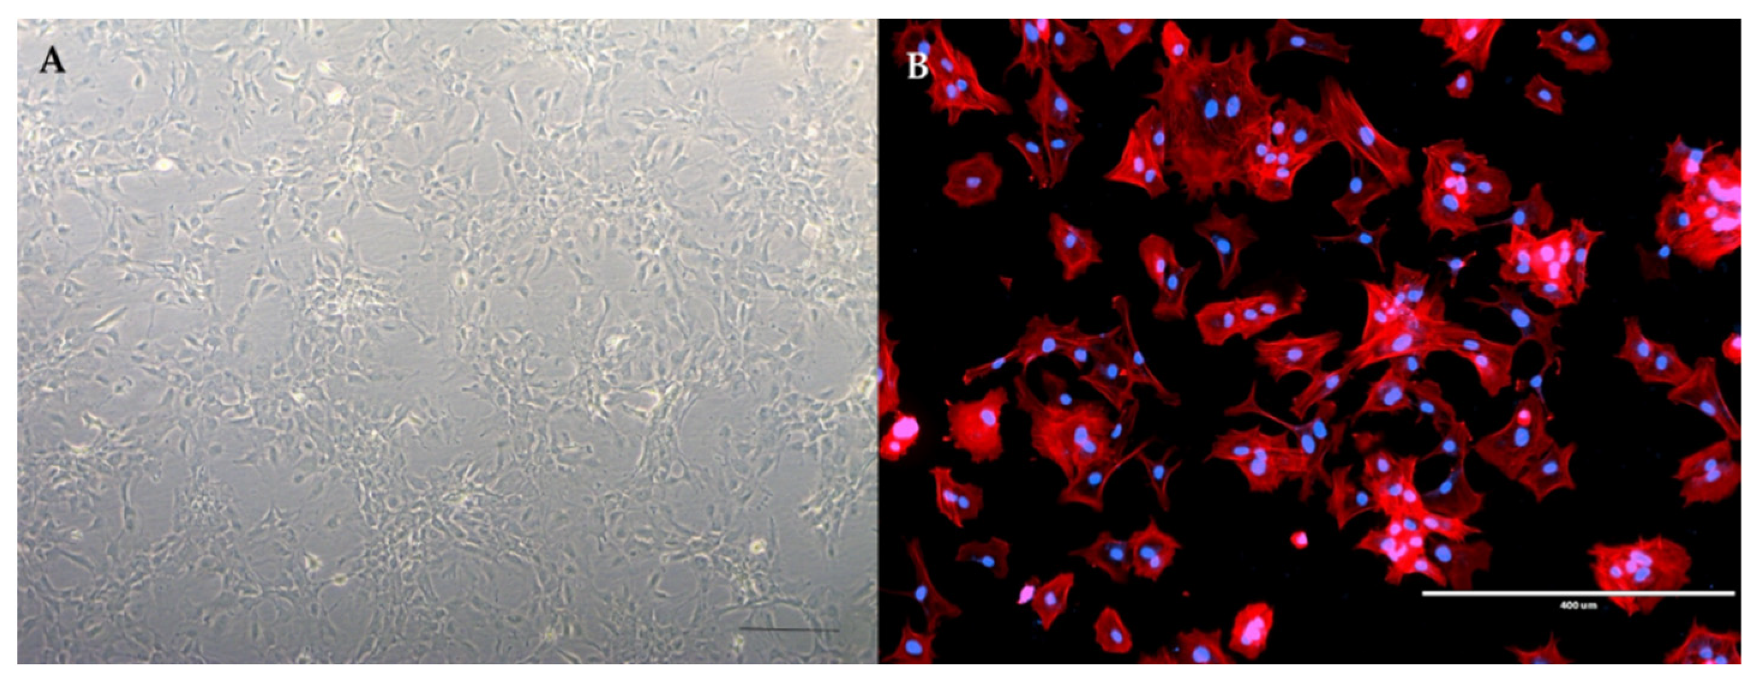

- Gradisnik, L.; Maver, U.; Bosnjak, R.; Velnar, T. Optimised isolation and characterisation of adult human astrocytes from neurotrauma patients. J. Neurosci. Methods 2020, 341, 108796. [Google Scholar] [CrossRef]

- Velnar, T.; Maver, U.; Bosnjak, R.; Gradisnik, L. The Isolation of Human Glioblastoma Cells: An Optimised Protocol. Acta Med. Acad. 2020, 49, 4–13. [Google Scholar] [CrossRef]